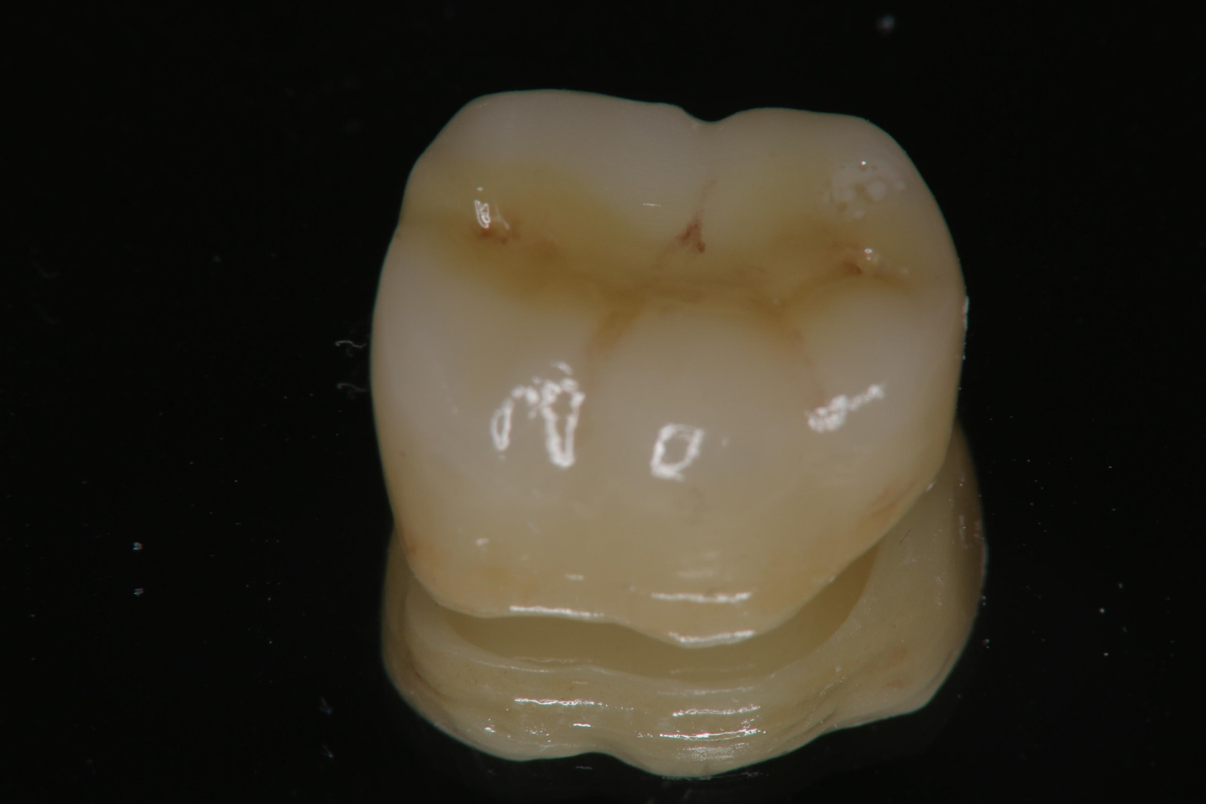

全鋯冠